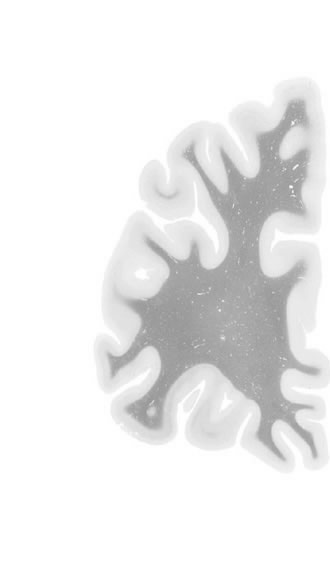

Frontal sections (Nissl) from the Atlas Brain:

Slice

Microscopy

Slice ID:

r1-0225

Plate NR:

04-05

Position:

-39,7 mm